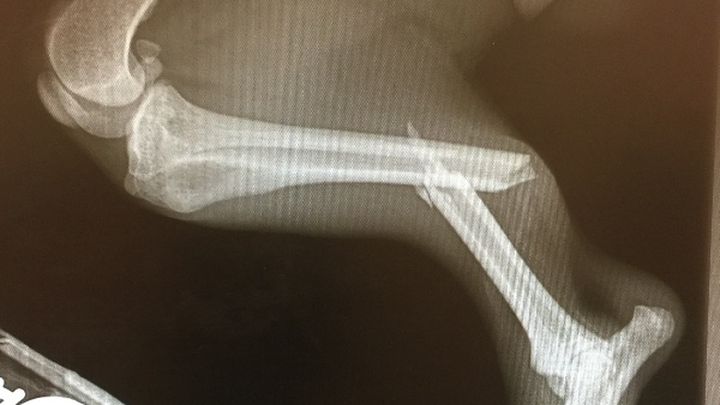

My husband and son quickly got in the car to chase him as he is really fast. Unfortunately, Chase decided to run onto a busy street and ran into the back of a vehicle breaking his leg. He still did not want to be caught and continued running until my son was finally able to catch up to him. They noticed right away that his back right leg was flopping around. They called me as I was away from home and I came home as quick as I could.

Of course this happened on a Saturday afternoon and our normal vet we see is closed. I took him to a local ER veterinarian to X-ray his back leg to see how bad it is. Chase was in shock and they put him on IV fluids and medicine to help calm him down, treat his pain and to finish assessing him.

After taking the X-ray, we discovered he snapped his back right leg in half. The ER vet quoted me $3000 to $4000 to have surgery to fix his break during the week when they had more staff on hand. They would charge around $1500 to $2000 to amputate his back leg if we chose to go that route. She told me low income veterinary offices might charge close to $700 to amputate and I might want to call around on Monday to see what I can find if I chose for them to not operate on Chase.